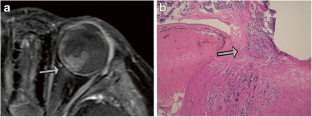

Fig. 1